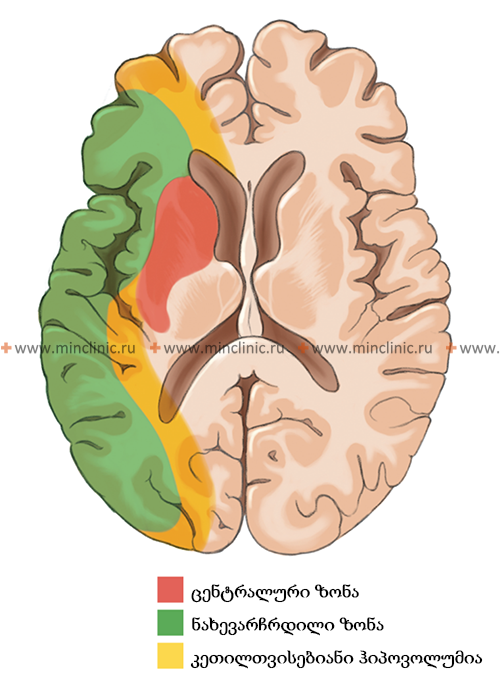

კლინიკური გამოსავალი დიდად არის დამოკიდებული თავად ემბოლზე და პაციენტის სისხლძარღვოვან ანატომიაზე [1]. ემბოლის ზომა, ლოკაცია და შემადგენლობა (მაგ., კოლტი, ცხიმი, სიმსივნე) განსაზღვრავს, რომელი ცერებრული არტერია დაიხშობა და, შესაბამისად, განვითარებული ცერებრული ინფარქტის (ინსულტის) მასშტაბსა და ლოკაციას [1, 2]. დიდი ემბოლები (მაგ., 2-3 მმ ან მეტი) უფრო მეტად ახშობენ დიდ სისხლძარღვებს, როგორიცაა ტვინის შუა არტერიის (MCA) ღერო, რაც პოტენციურად იწვევს ვრცელ ინფარქტს, რომელიც მოიცავს თავის ტვინის ქერქს, ქვემდებარე თეთრ ნივთიერებას და რუხი ნივთიერების ღრმა სტრუქტურებს (ბაზალური განგლიები, თალამუსი) [1, 2]. უფრო მცირე ემბოლები შეიძლება გადაადგილდეს უფრო შორს დისტალურად, დაახშოს MCA-ის ან ბაზილარული არტერიის მცირე პერფორანტული ტოტები, რაც ხშირად იწვევს უფრო მცირე, ღრმა ინფარქტებს, რომლებიც ცნობილია როგორც ლაკუნური ინფარქტები (თუმცა ლაკუნური ინსულტები უფრო კლასიკურად ასოცირდება მცირე სისხლძარღვთა დაავადებასთან/ლიპოჰიალინოზთან, ვიდრე ემბოლიასთან) [1, 6].

მაგალითად, ადეკვატურმა კოლატერალურმა სისხლის ნაკადმა ვილიზის წრის გავლით ან ხერხემლის არტერიებიდან შეიძლება თავიდან აიცილოს ან მინიმუმამდე დაიყვანოს იშემია ან ინფარქტი მაშინაც კი, როდესაც ემბოლი ახშობს ისეთ მსხვილ პროქსიმალურ სისხლძარღვს, როგორიცაა შიდა საძილე არტერია, ტვინის წინა არტერიის A1 სეგმენტი ან პროქსიმალური ხერხემლის არტერია [7]. ანალოგიურად, ემბოლებმა, რომლებიც იჭედებიან კორტიკალურ ტოტებში ან თუნდაც ტვინის შუა არტერიის ღეროში, შეიძლება გამოიწვიოს შედარებით შეზღუდული კორტიკალური ან სუბკორტიკალური ინფარქტები, თუ არსებობს ძლიერი კოლატერალური ნაკადი ტვინის წინა ან უკანა არტერიების მიმდებარე აუზებიდან ტვინის ზედაპირზე არსებული ლეპტომენინგეალური კავშირების მეშვეობით [7]. კოლატერალური მიწოდების ეს პრინციპები ასევე ძალზე აქტუალურია უკანა ცირკულაციის ემბოლიის შედეგების განსაზღვრაში, რაც გავლენას ახდენს ტვინის ღეროსა და ნათხემზე [1, 7].

როდესაც გული ცალსახად იდენტიფიცირებულია, როგორც ემბოლიური წყარო, კვლევები მიუთითებენ თავის ტვინში განაწილების გარკვეულ პატერნზე. გულისმიერი ემბოლების დაახლოებით 80% მიდრეკილია გაიჭედოს ტვინის შუა არტერიის აუზში (რადგან ის იღებს საძილე არტერიის სისხლის ნაკადის ყველაზე დიდ ნაწილს), დაახლოებით 10-11% შეიძლება გადაადგილდეს ტვინის უკანა არტერიის აუზში (უკანა ცირკულაციის მეშვეობით), ხოლო დანარჩენი ნაწილდება ტვინის წინა არტერიის აუზში ან უშუალოდ ხერხემლის ან ბაზილარულ არტერიებში ან მათ ტოტებში [1, 2].

- სუპრატენტორიული შეშუპება: ემბოლიური ინფარქტების დროს, რომლებიც აზიანებს თავის ტვინის ნახევარსფეროებს (სუპრატენტორიული), ინფარქტის უფრო დიდი ზომა პირდაპირ კორელაციაშია ცერებრული შეშუპების გაზრდილ რისკთან და სიმძიმესთან. დიდი ემბოლების მიერ MCA-ის ღეროს ოკლუზია განსაკუთრებით მიდრეკილია გამოიწვიოს მნიშვნელოვანი შეშუპება ("ავთვისებიანი MCA სინდრომი"), რამაც შეიძლება გამოიწვიოს ქალასშიდა წნევის მომატება, შუა ხაზის ცდომა, ტვინის ჩაჭედვა (განსაკუთრებით საფეთქლის წილის ჩაჭედვა), კომა და სიკვდილი, თუ აგრესიულად არ იმართება. მცირე ტოტების დამაზიანებელი ემბოლები ტიპურად იწვევს ნაკლებ შეშუპებას.